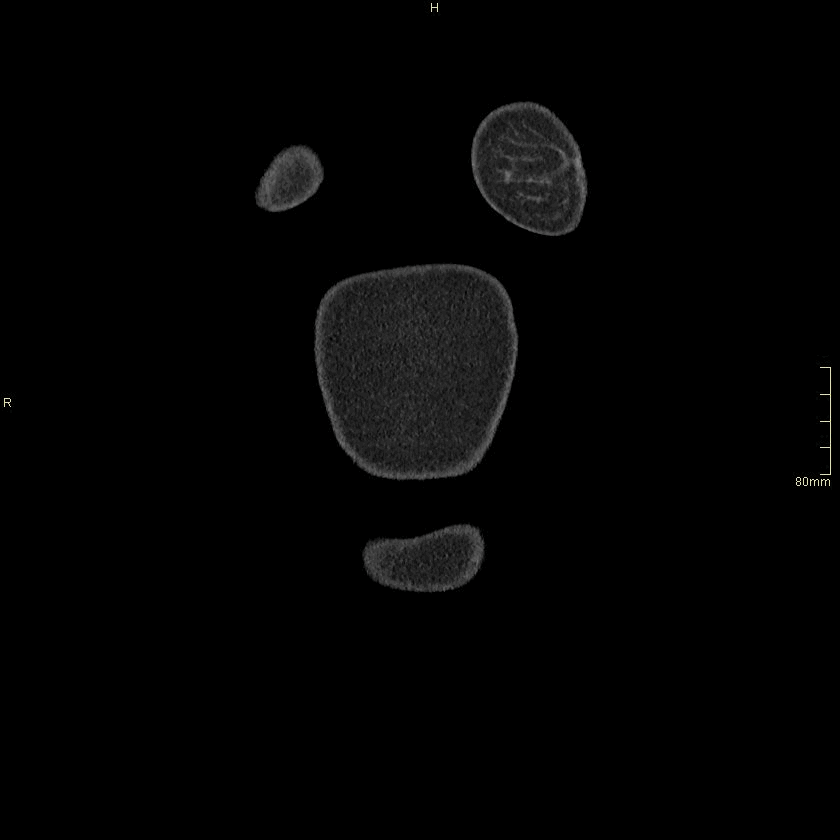

Example below is a General Chest/Abdo/Pelvis without contrast. Bony reconstructions are available depending on clinical question and differential diagnosis

Chest/Abdo/Pelvis (Axial)

Lung (Axial)